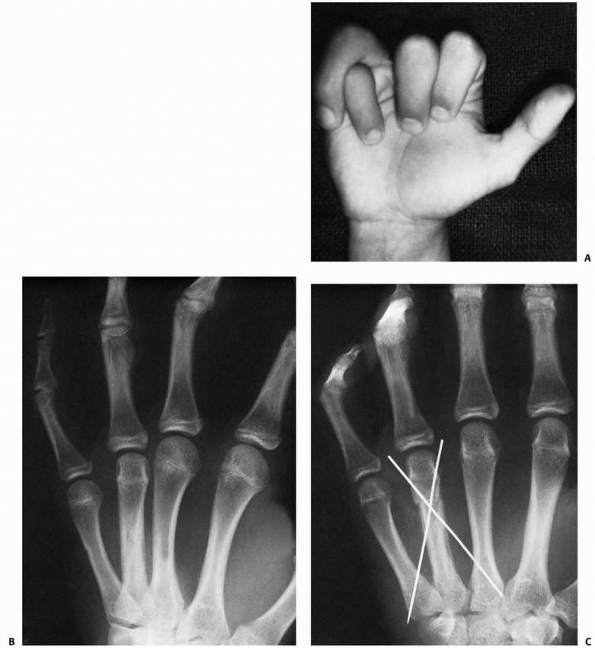

FIGURE 8-29 A. An extra-octave fracture in a 12-year-old girl. B. The fracture was reduced with the MCP joint in full flexion.

|